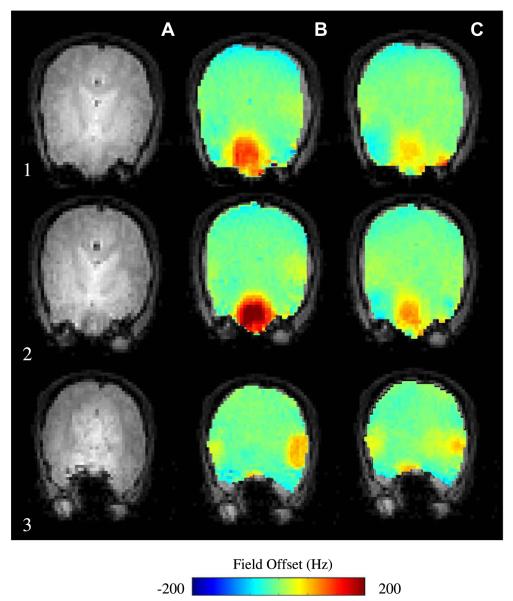

Fig. 8 shows the effects of increasing orders of shim inclusion in the whole-brain least-squares optimization of B0 field homogeneity in the human brain at 3T. It is clear from the field-maps that low-order RT shimming leaves significant residual inhomogeneity. While there is a clear advantage of going from first (B) to second (C) order shimming, with the use of third-order shimming (D), there is significantly less improvement in homogeneity compared to second-order shimming (C).

Fig. 8.

(A) Axial MRI at B0 = 3T of two axial slices encompassing the sinus cavity region, residual inhomogeneity after (B) first order shimming, (C) with the inclusion of second-order shims, (D) with the inclusion of third-order shims.

Fig. 9 similarly shows residual field maps after global shimming of the mouse brain at 9.4T. The residual inhomogeneity here is even more severe than in the human case due to (a) the higher magnetic field strengths of small-animal MR systems and (b) the more complicated air-cavity distributions in the mouse head. Viable high-field, whole-brain, single-shot EPI images of the mouse brain have yet to be demonstrated because of this residual inhomogeneity. This severely limits the quality and temporal resolution of BOLD and DTI studies on the mouse brain.

Fig. 9.

Coronal field inhomogeneity maps of the mouse brain at 9.4T with (A) no shimming, (B) first-order shimming, (C) first and second-order shimming, and (D) first through third-order shimming.